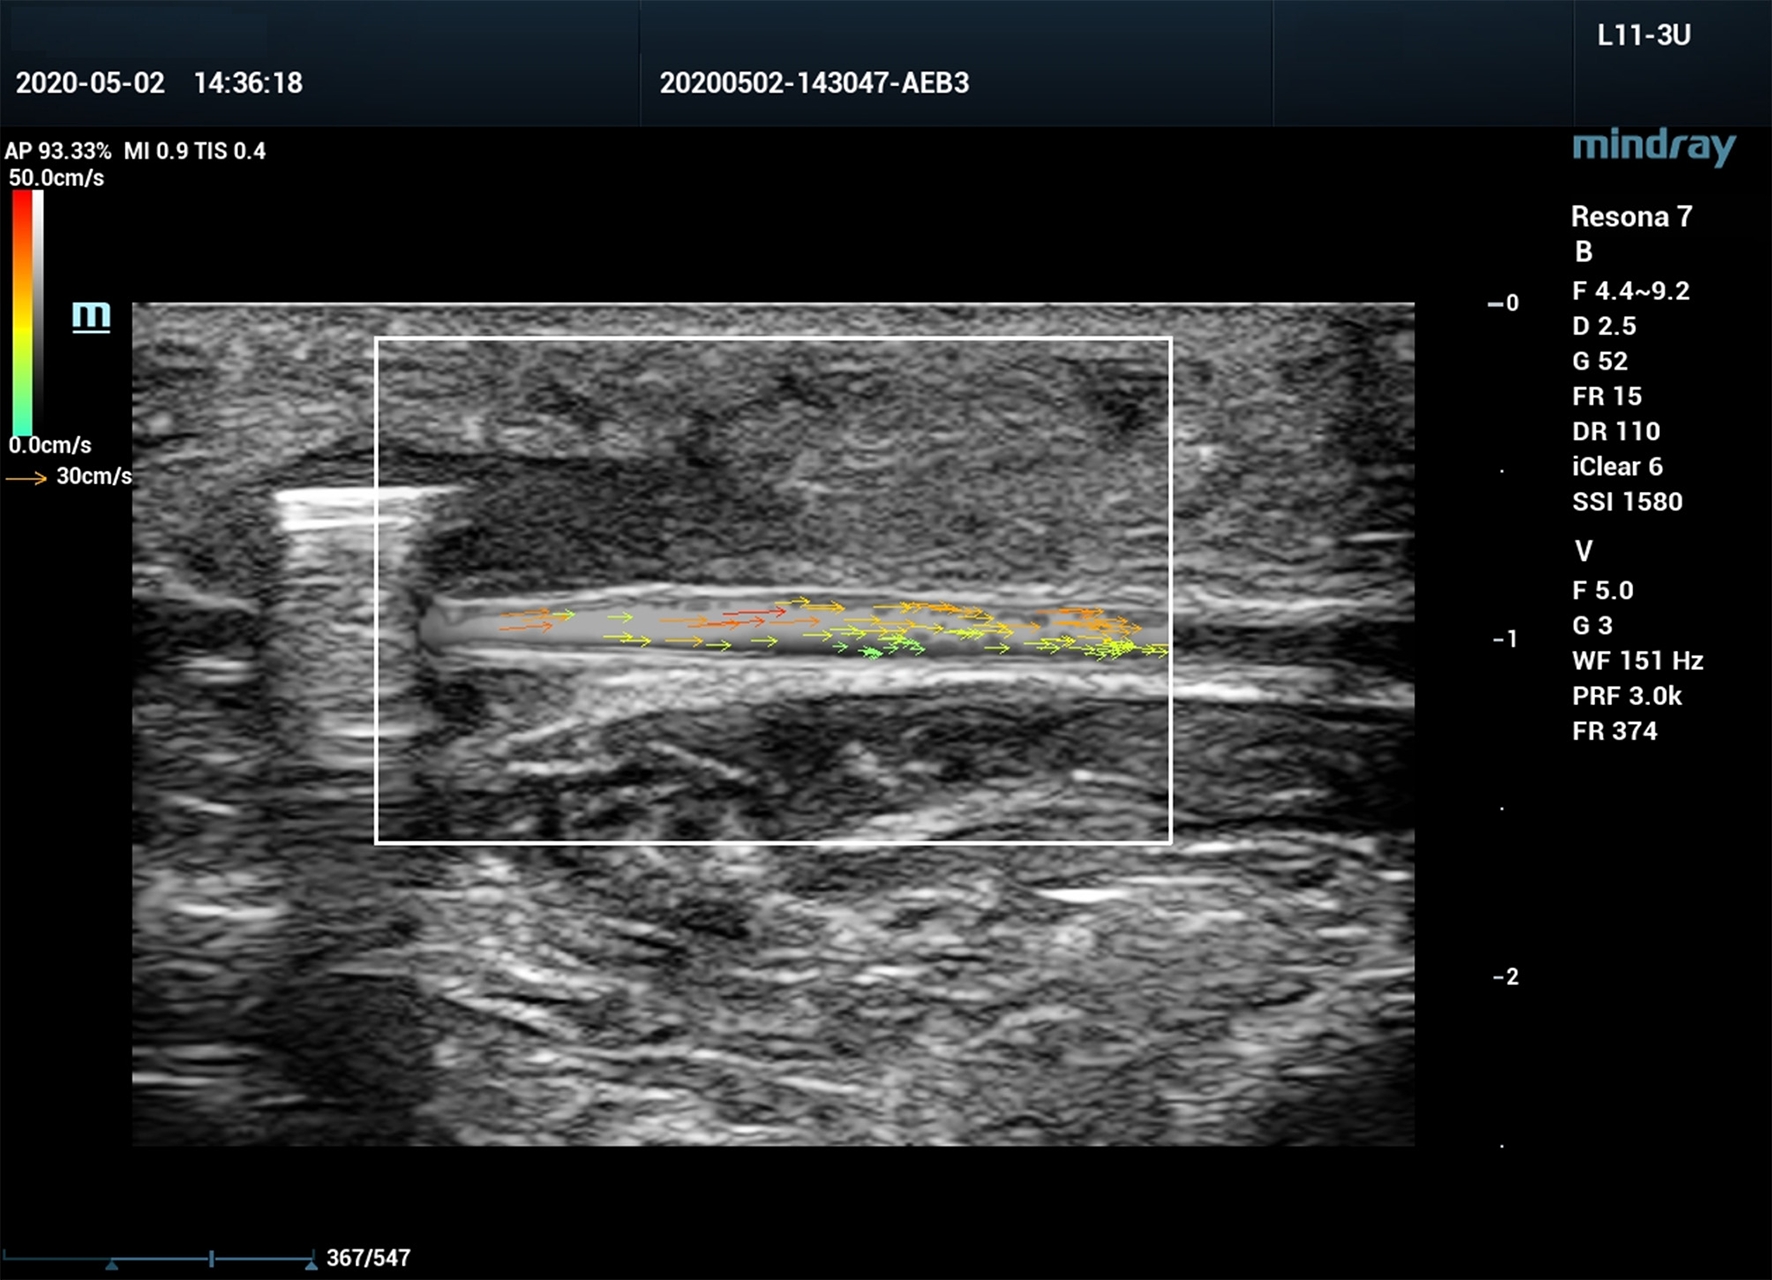

Figure 5

V Flow ultrasound image of a canine femoral artery with post-stenotic segment spasm.

Post-stenotic Tur indices distal to a 70% stenosis are shown in Table 3. Post-stenotic segment spasm occurred in Case 2. The PSVs in the segment were ranged from 128 cm/s to 198 cm/s, and the Tur index (<1%) occurred in 9 of 10 measurement sites (Table 3 and Figure 5). This case is not included in the calculation for mean, standard deviation, number of cases with Tur <1%, number of cases with Tur>1%, and number of cases with maximum Tur. In the remainder of 11 cases, the Tur index (>1%) was 81.8–100% between 1 and 17 mm distal to the stenosis, and 63.6% at 19 mm (Table 3 and Figure 3). Figure 6 shows Tur index changes in relation to distances distal to a 70% stenosis. Based on a canine femoral artery diameter of 3 mm, post-stenotic Tur index increased immediately distal to the stenosis and reached its maximum value at 5–11 mm or 1.7–3.7 diameters downstream in all 11 cases (100%) followed by a decrease (Table 3 and Figure 6).